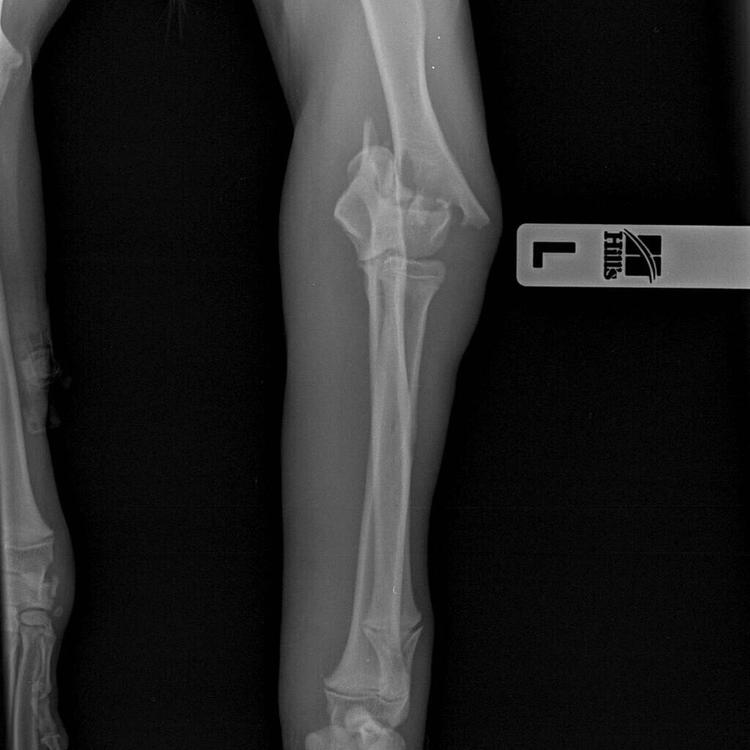

Stenveyz Опубликовано 19 мая, 2019 Опубликовано 19 мая, 2019 Где 6? 5 на передних я вижу, и 4 на задней. Вторая лапа не видна. Вот вчерашнее обновления в группе фонда.

Лея и мама Опубликовано 20 мая, 2019 Опубликовано 20 мая, 2019 Малыш абсолютно чудесный! Ласковый и трепетный. Прижимается к ноге и замирает от счастья что он не один. В машине стал весело погрызывать мне руку) очень не хочет быть один. Как только остался один в комнате поднял шум) но очень быстро успокоился. Лечить нужно и вторую лапку. После катетера осталась плохая рана. Сейчас ее обрабатывают и закладывают мазь. Ну ничего! Будем лечиться. Завтра утром поеду проведывать малыша. Спасибо всем неровнодушным, тем кто участвует в жизни малыша словом, делом и денежкой!